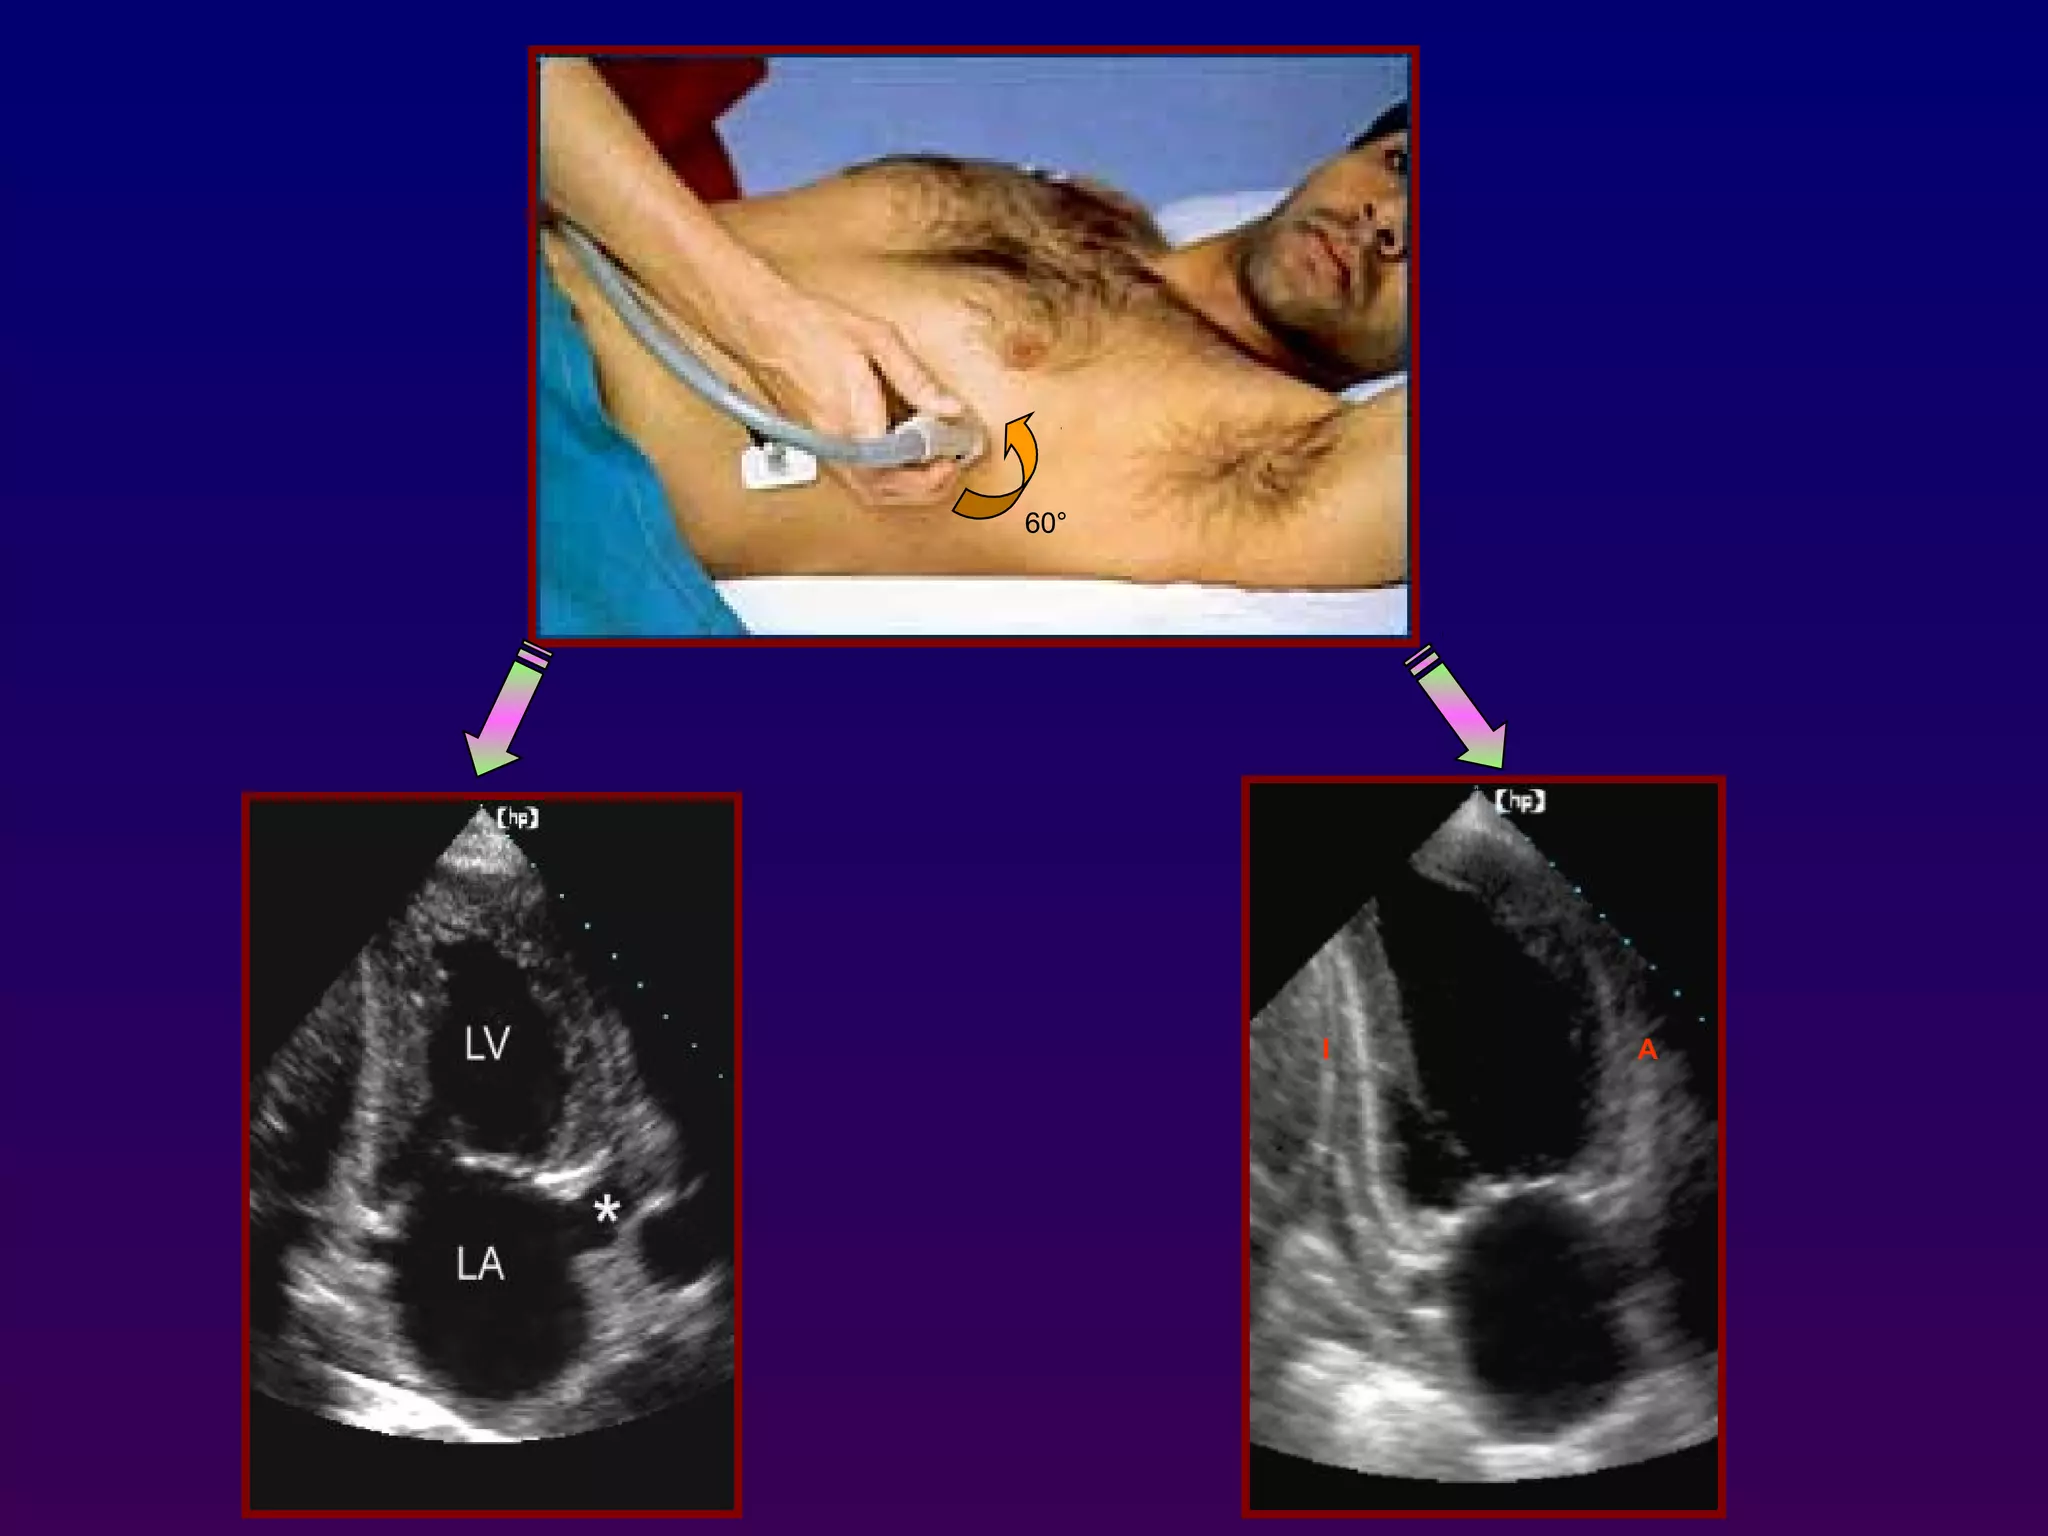

Apical two-chamber

Counterclockwise rotation from the apical

fourchamber orientation 60° results in

acquisition of the apical two-chamber view

In this orientation, the inferior and anterior

walls of the left ventricle are visualized,

along with the left ventricular apex and left

atrial chamber.

60°

I A